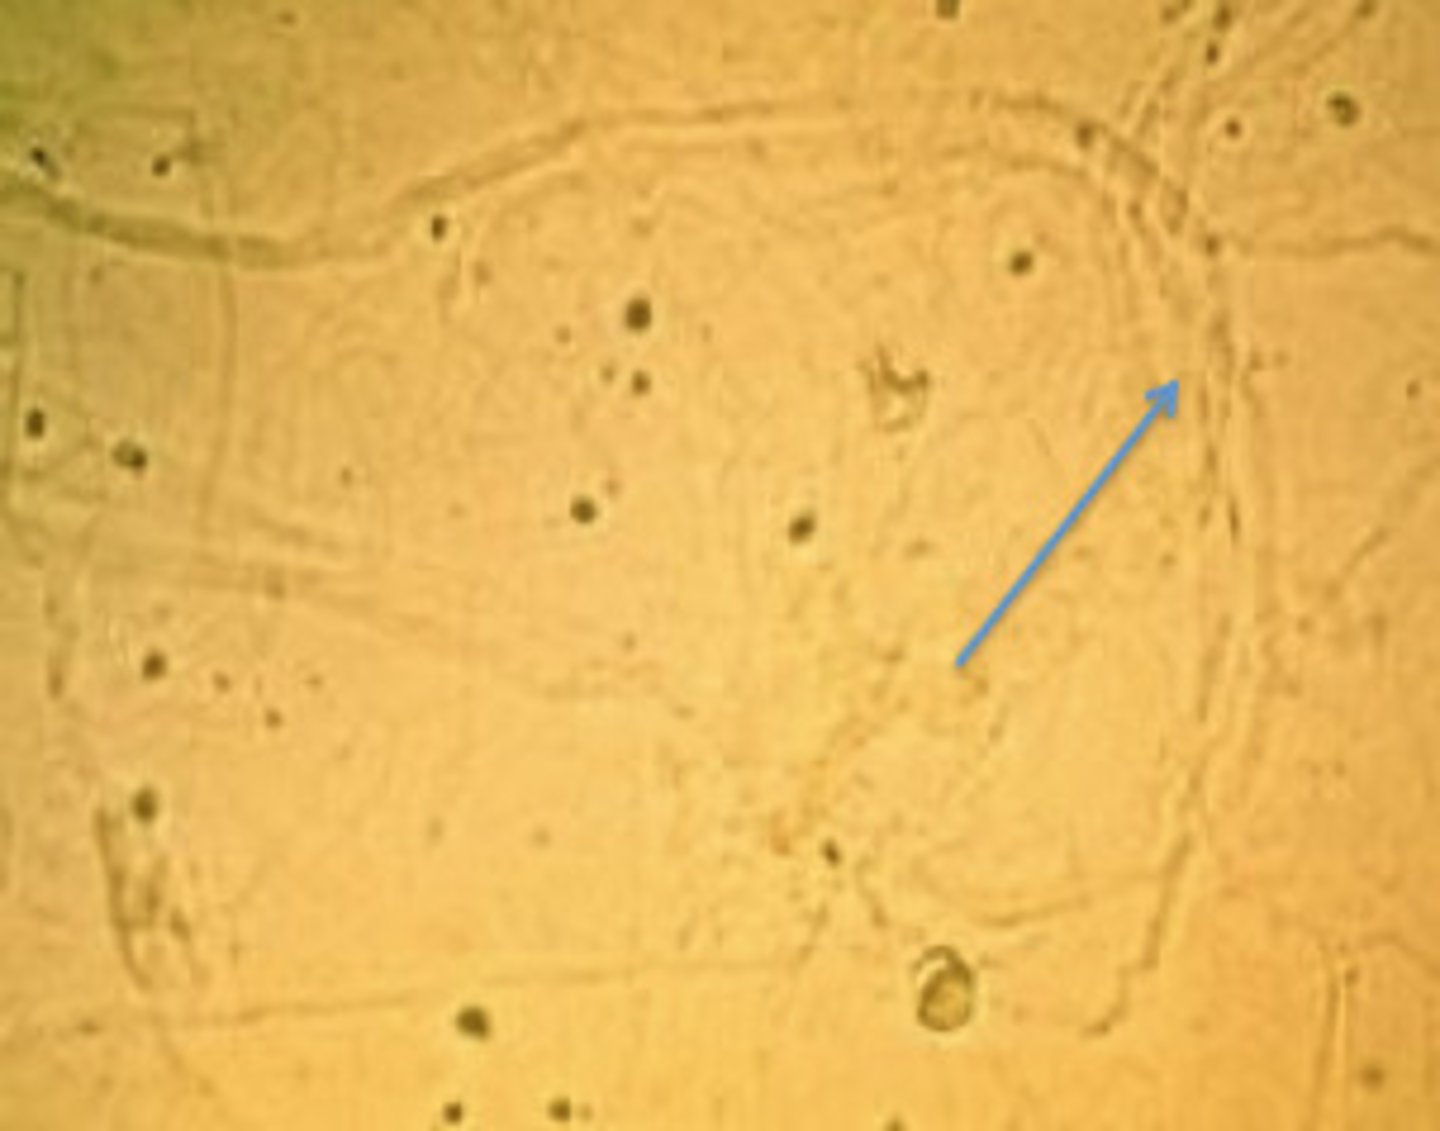

Mucus